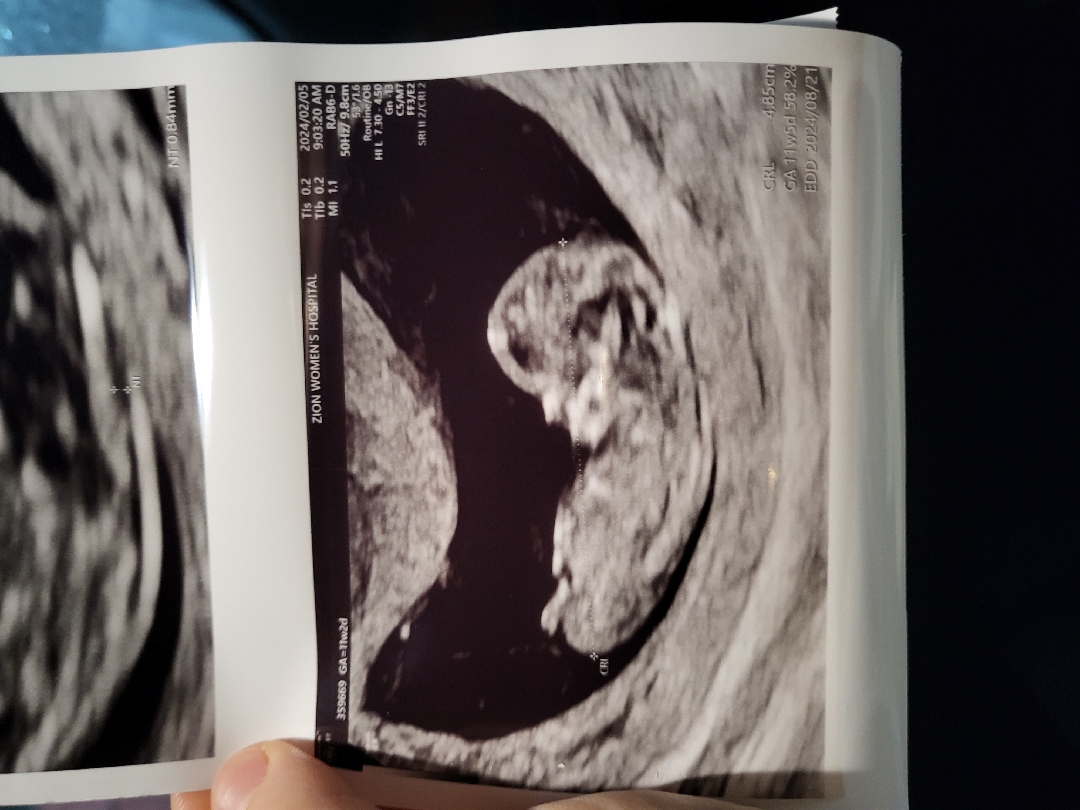

띠용이 너모기엽죠??? 자랑할라고 왔는데 요상태로도 성별이 보이시나요?? 선배님들 속삭여주세용ㅋㅋㅋㅋㅋㅋㅋ 아들이던 딸이던 다좋지만 !!!!!

그쵸!!! 1차기형아검사하러 갔는데 저만큼 컷더라구용 넘 신기했어요 아직 피부가 안생겨서 뼈만 저렇게 보이네용 ㅎㅎ

초음파사진 보니 11주5일이네요~ 쪼오금더 기다려보셔요 : )